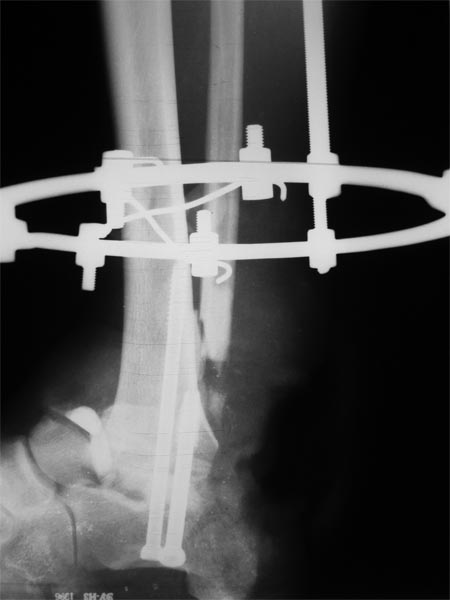

Уважаемые коллеги! Как и обещал представляю результат лечения пациента с дробовым

ранением,который обсуждался в теме http://weborto.net/forum/1350149570/index_html.

Фото содержатся во вложенном файле. Пациенту для закрытия дефекта выполнена резекция

таранной кости, пяточно-большебецовый артродез винтами. После укорочения сформировался

запас тканей, достаточный для закрытия дефекта. Далее несколько дней повязка с низким

давлением и свободная аутодермопластика. Пациент выписан. После окончательного

заживления планируем демонтировать аппарат и перейти на циркулярную повязку. Когда по

Вашему мнению следует давать нагрузку?